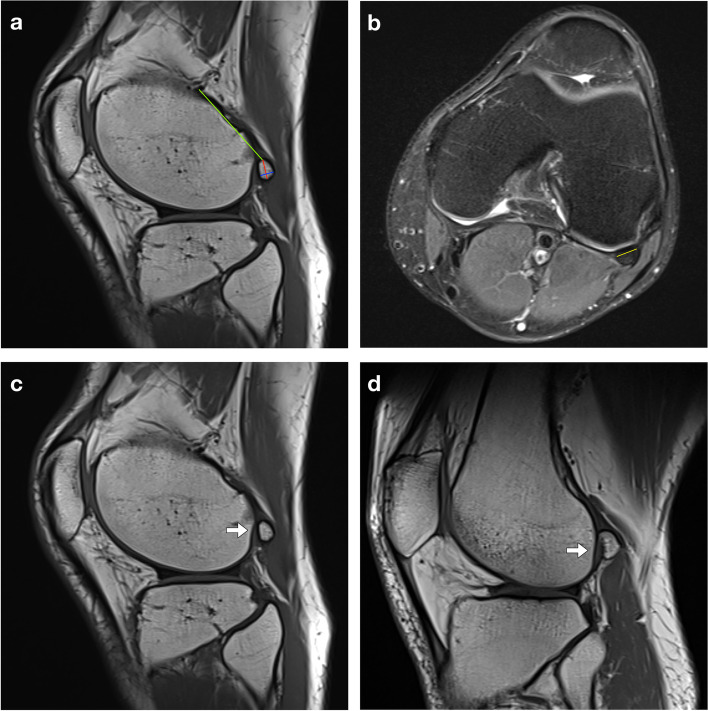

In patients where a fabella was present, two readers (one radiologist with 4-year-experience and one orthopedist with 3-year-experience) independently measured the parameters of the fabella, including the maximum length, thickness and width, and distance between the fabella and the insertion of the lateral head of the gastrocnemius onto the femur (DFI), based on MRI films on sagittal, coronal or axial views of the knee [5, 14] (Fig. 2a-b). The intraclass correlation coefficient (ICC) was used to assess the interobserver reliability, while measurements in a random sample of 50 knees were repeated by the radiologist 2 weeks later to assess intraobserver reliability. We chose ICC (2,1) for measurement reliability assessment according to Koo et al. [15]. The presence of any articulating groove was documented, which was defined as either a flat or concave contour of the lateral femoral condyle (Fig. 2c-d). The definition and measurements were described previously [14]. The length/thickness ratio, width/thickness ratio and length/width ratio of fabellae were calculated to present their morphology.

Fig. 2.

Magnetic resonance imaging (MRI) measurement and articulating groove. a Sagittal MRI of the knee shows the measurement of the maximum length (red line), thickness (blue line) of fabella, and the distance between the fabella and the insertion of the lateral head of the gastrocnemius onto the femur (green line); b Axial MRI of the knee shows the measurement of the maximum width of the fabella (yellow line); MRI of the knee show (c) concave and (d) flat contours of the articulating groove of the lateral femoral condyle of the femur (arrow)